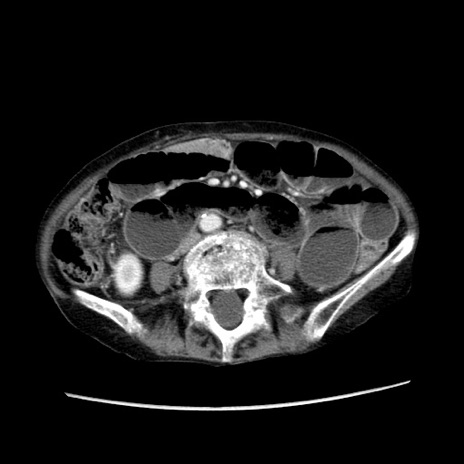

症例25(横断像)

【症例】80歳代女性

【主訴】胸のつかえ感

【現病歴】約9時間前に食後から胸のつかえた感じあり、嘔吐あり、来院。

【既往歴】胃癌(全摘)、胆摘、虫垂炎

【身体所見】心窩部に圧痛あり、反跳痛なし。

【データ】WBC 5700、CRP 0.05